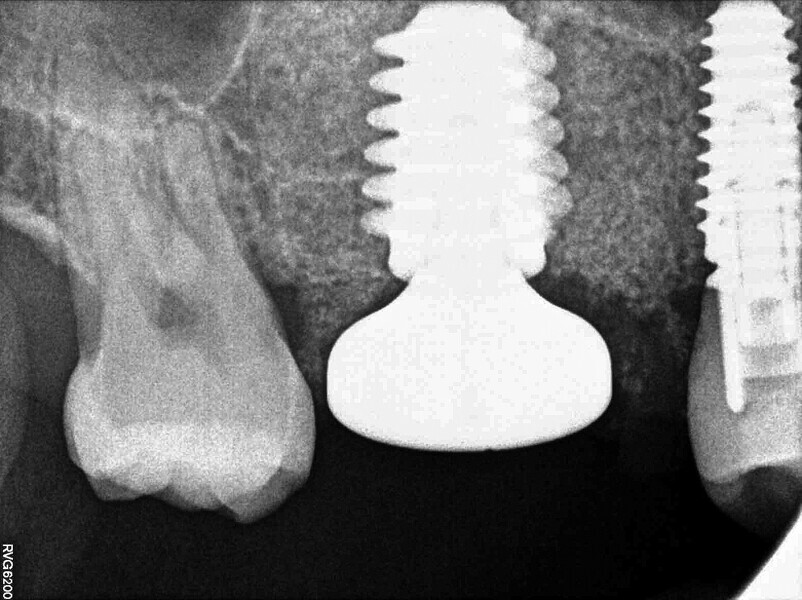

Digital workflow and application of PRF and ozone therapy in oral rehabilitation